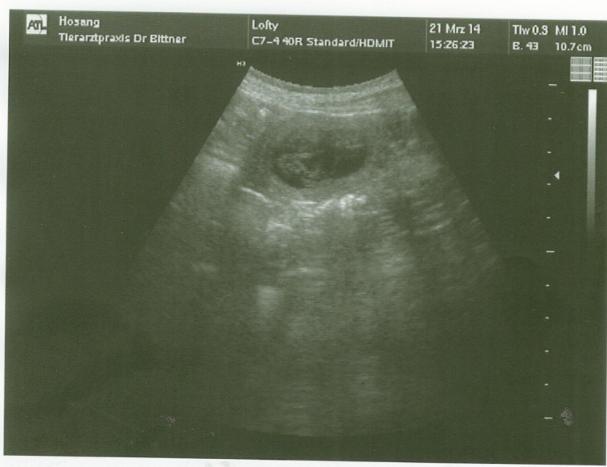

Am 21.03.2014 waren wir mit Lofty beim Ultraschall und jetzt steht es fest - wir bekommen Babys !